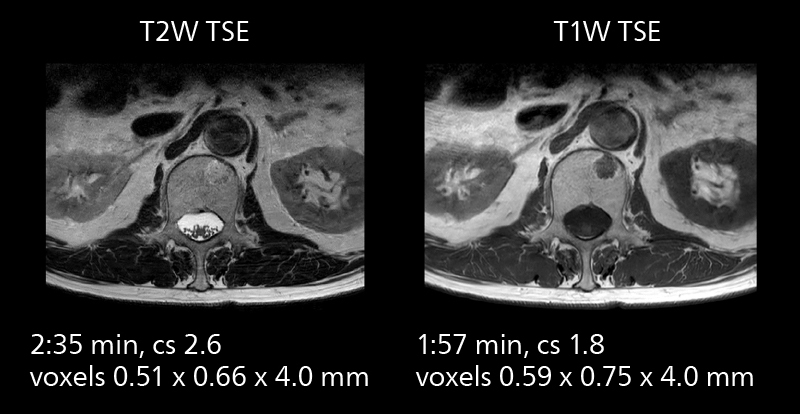

Examples of prostate imaging showing faster scan times and improved resolution illustrate the power of SmartPath to Elition X in this case of prostate cancer with PI-RADS score 4.